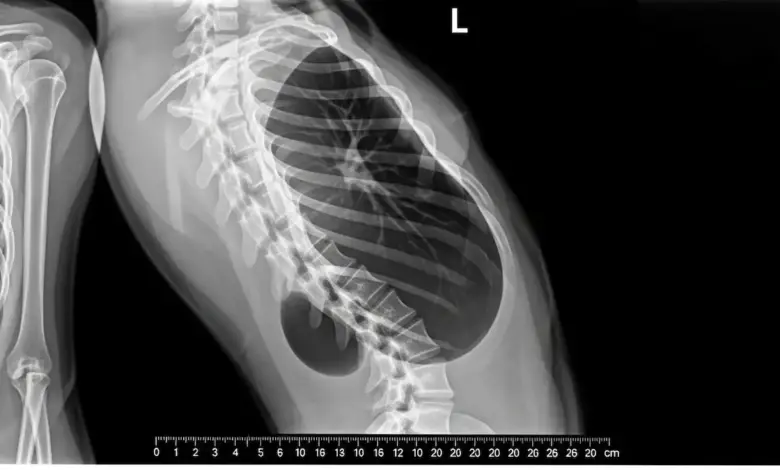

Os exames de imagem confirmam a presença da hemivértebra e esclarecem a gravidade da deformidade. Em geral, são solicitados:

- Radiografias panorâmicas da coluna em pé, para medir o grau da curva e localizar a hemivértebra;

- Tomografia computadorizada, que mostra com precisão o formato das vértebras e a anatomia óssea;